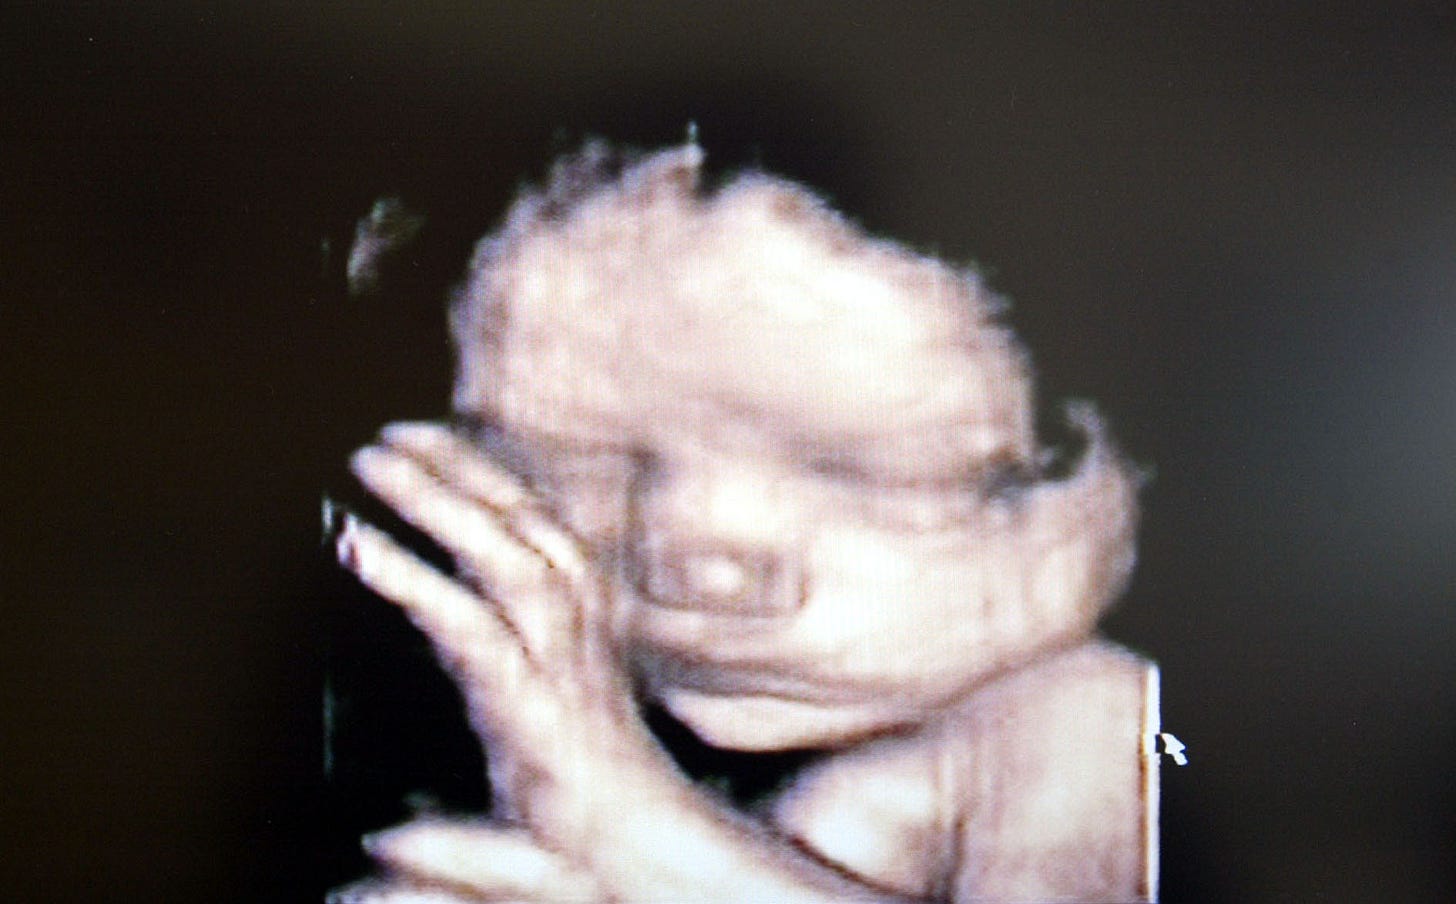

The term "unborn" implies that there is a baby inside a pregnant woman, not a fetus. Babies are not babies until they are born. They're fetuses. Incorrectly calling a fetus a "baby" or "the unborn" is part of the strategy used by antiabortion groups to shift language/legality/public opinion.

This might be the most inane argument ever made in the entire insane history of America’s abortion debate. The terms fetus and baby are not mutually exclusive. Fetus is a noun, yes, but one that describes a stage of human development. Just like infant or toddler or adolescent. The only reason to argue that a “fetus” is not a “baby” is to spitefully deny its humanity. And by the by, if it’s medically incorrect to refer to a fetus as a baby, someone should alert textbook editors, science journalists, every obstetrician ever, the maternity industrial complex, and, um, Planned Parenthood. Also, the claim that using the word “baby” is some nefarious “strategy used by antiabortion groups to shift language/legality/public opinion” gives the lie to the idea that NPR seeks to be at all fair or impartial on this issue. There is no passage warning against euphemisms preferred by the pro-choice movement, like “terminating a pregnancy” or “reproductive health care.” There are no calls to “consider the strongest arguments we can find on all sides” or be “sensitive to differences in attitudes and culture.” Nope, it’s clear that, on this one issue, there are good guys and there are bad guys. In this case, it’s the “bad guys” who want to be compassionate toward other people.